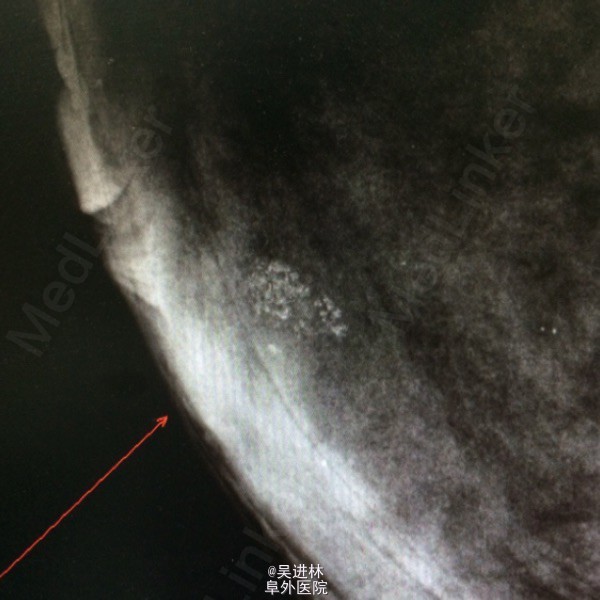

今天本来打算继续腹膜后脂肪肉瘤,但是悲闻姚贝娜因癌去世,遂借以下病例来谈谈乳腺癌钙化特点:患者中年女性,慢性起病,双侧乳房肿物4年余,以“双侧乳腺癌可疑”收入院。一般女性绝经候乳腺腺体开始萎缩,而此人腺体高度发达,脂肪组织几乎不可见,也是令人称奇(见钼靶)。查体双乳均可触及肿块,质硬,境界清,无压痛,表面欠光滑。腋下淋巴结未触及。钼靶显示双侧均可见簇状钙化。术前几乎被当作双侧乳腺癌来教学查房了一番,术后病理提示乳腺腺病。